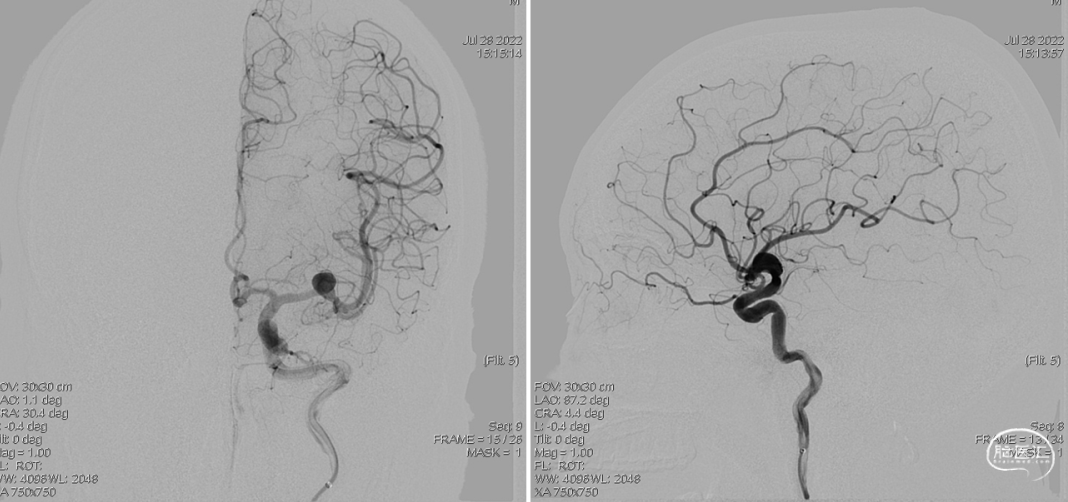

DSA检查:L-M1段夹层动脉瘤(07-28)。

术中2-D造影可见远端血管通畅良好,晚期动脉瘤内造影剂滞留明显。(07-28)

正位

侧位

动脉瘤明显缩小,仅小部分动脉瘤显影,3D可见支架打开充分贴壁良好。

正位

侧位